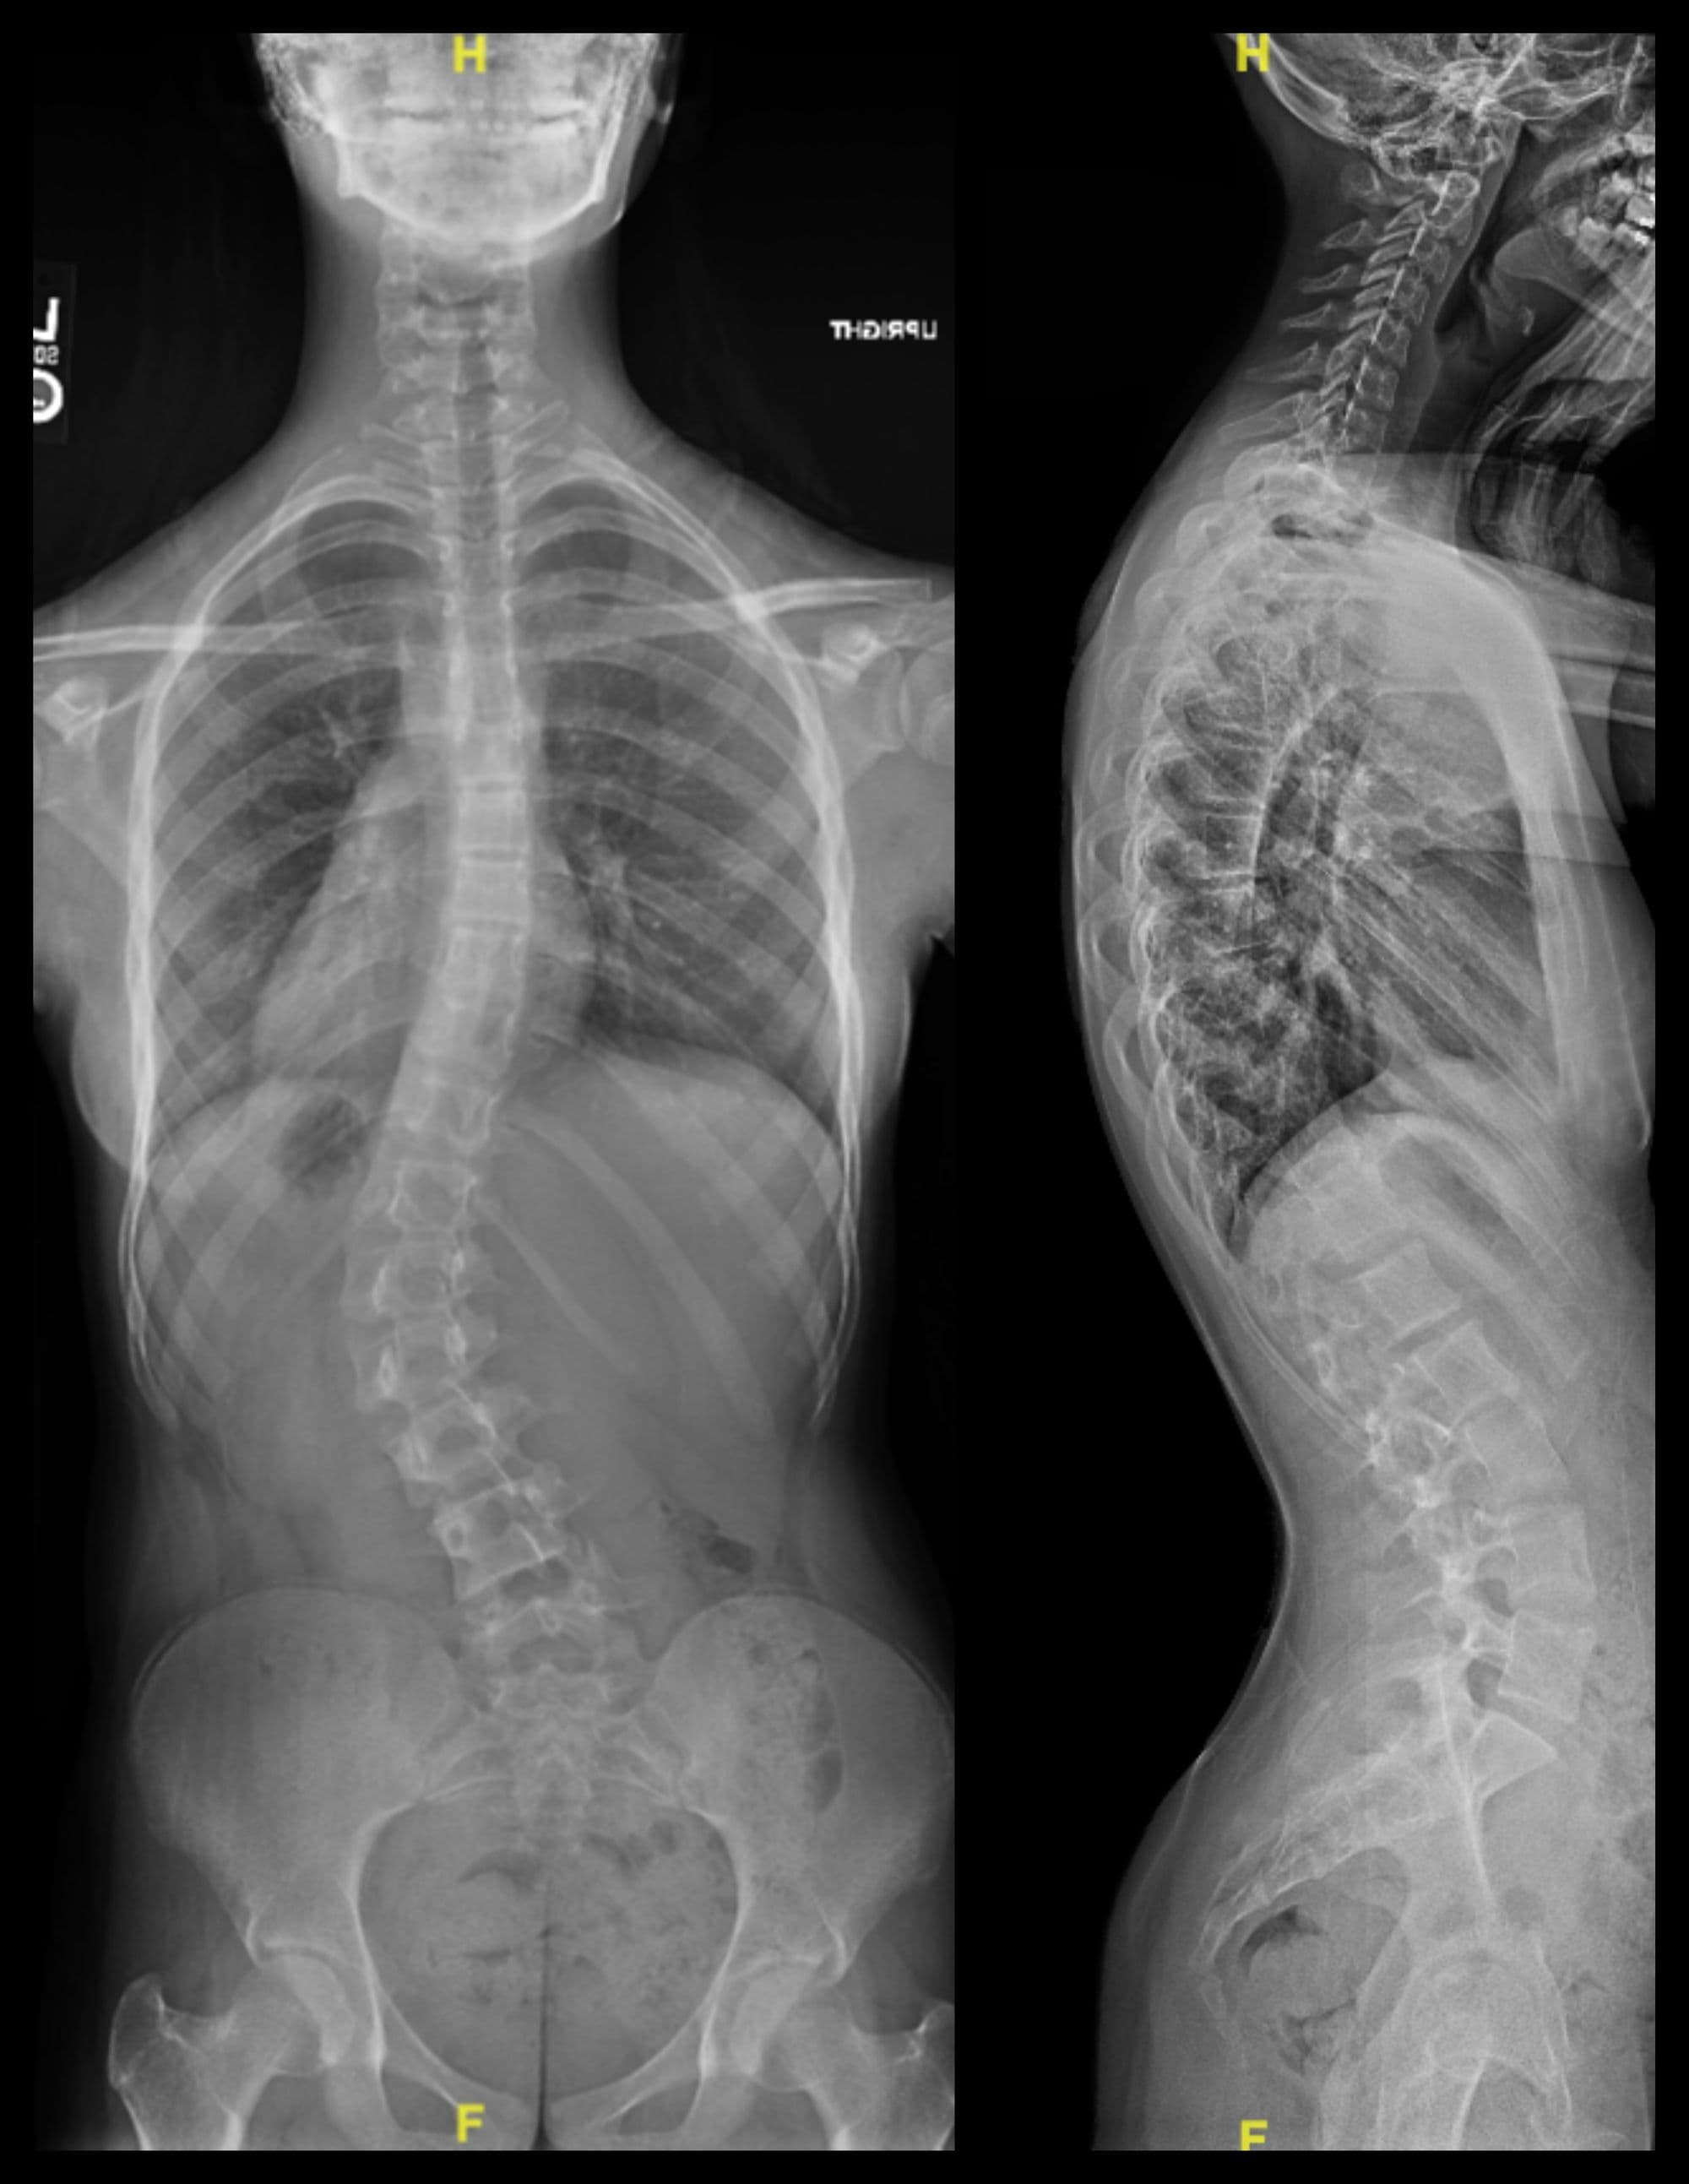

Posterior Spinal Fusion for Scoliosis

Anthony Scaduto